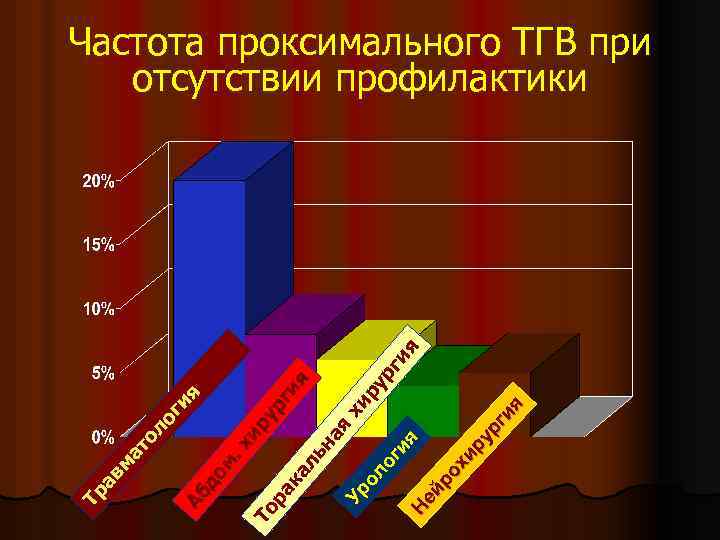

Тр ав м ат ол ог ия Аб до м. хи ру То рг ра ия ка ль на я Ур хи ол ру рг ог ия ия Н ей ро хи ру рг ия Частота проксимального ТГВ при отсутствии профилактики